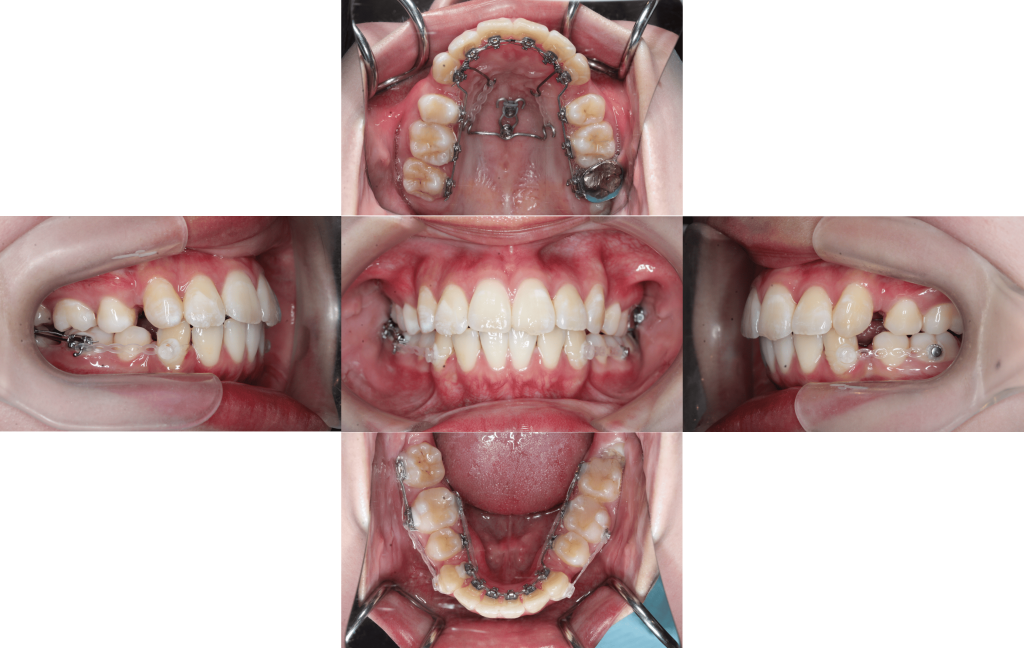

Before

After

初診

装置装着

約6か月後

約1年後

約1年6か月後

約2年後

約2年6か月後

約3年後

年齢層

20代

性別

女性

主訴

・1┴1でっぱり・凸凹な歯並び・Eライン・上下のかみ合わせ

治療費用

¥1,320,000

治療期間

約3年(治療中)

抜歯

上下顎両側第一小臼歯

矯正の装置

マルチブラケット装置(裏側矯正)

副作用、リスク

歯肉退縮,歯根吸収,疼痛,咬合の違和感,装置の違和感,虫歯,歯肉炎